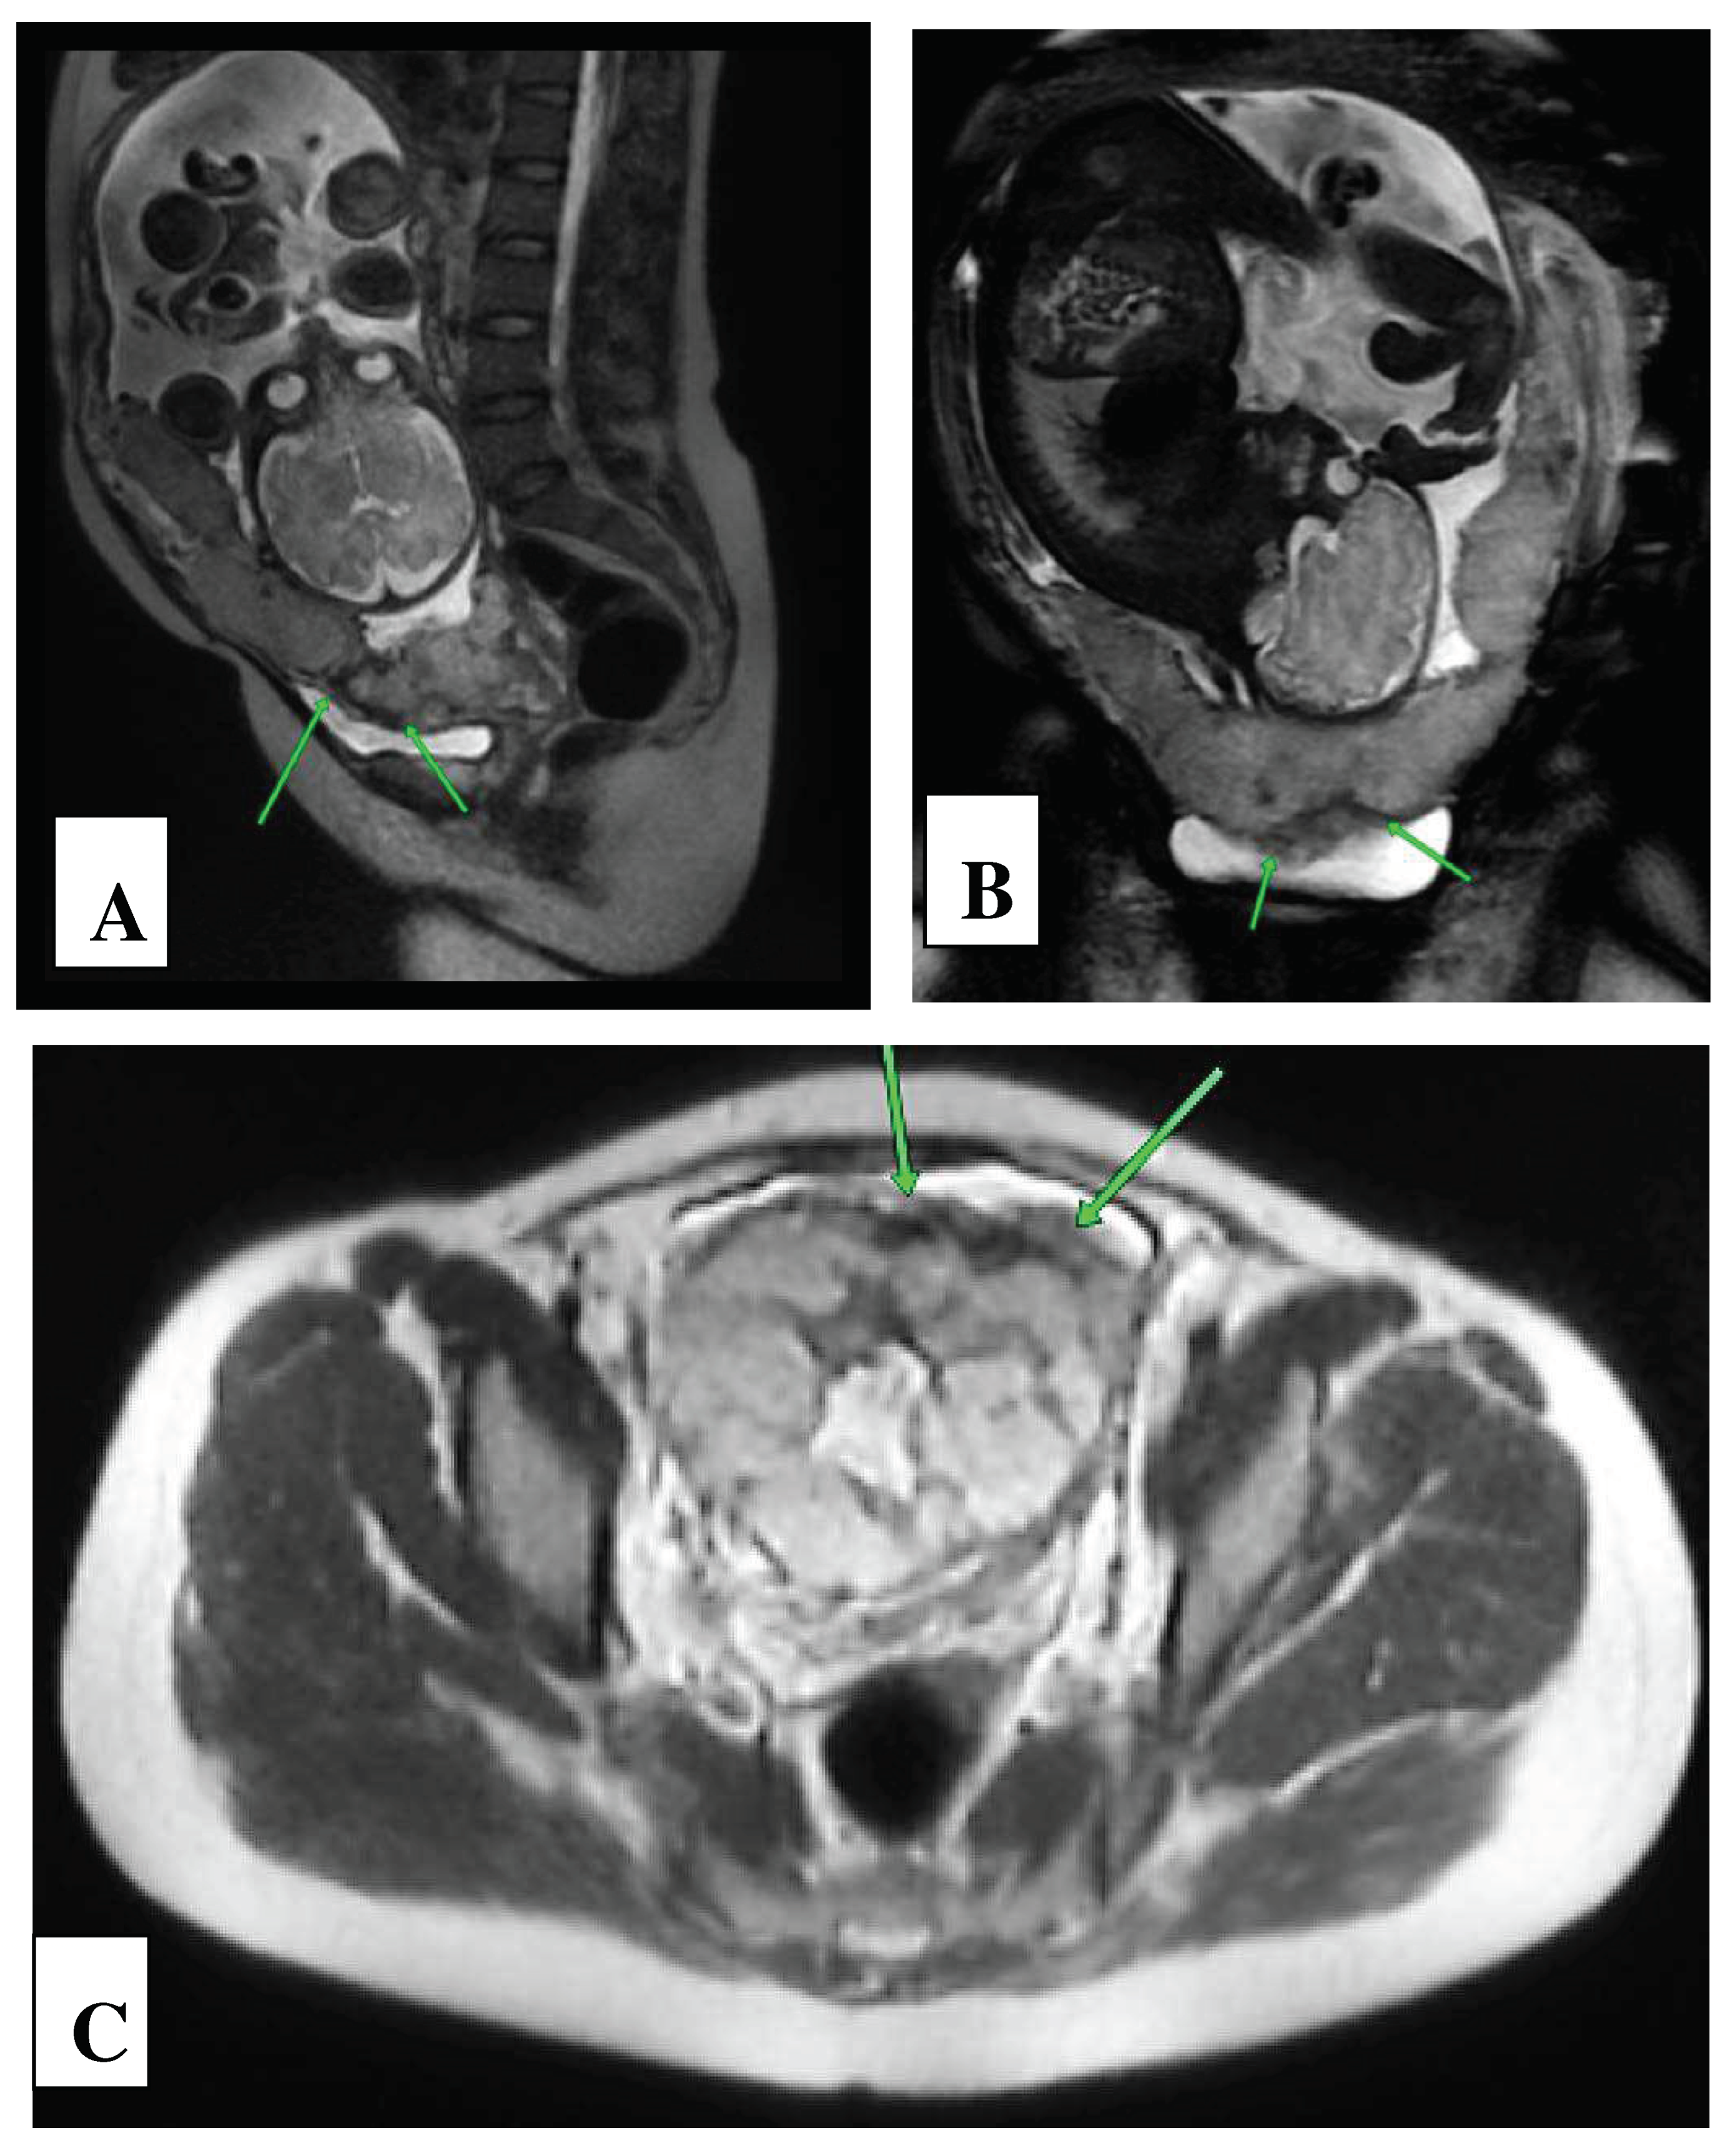

| Basic signs: | Availability | MAPI Scores - RADS |

|---|---|---|

| Local prolapse of the uterine wall («uterine hernia») | present | 2 |

| Thinning of the myometrium in the area where the placenta adjacent | present | 2 |

| MRI vascular lacuna visualization in the structure of the placenta | present | 2 |

| Vascular band MRI visualization in the structure of the placenta | present | 2 |

| Retroplacental hypointense “shadow” | present | 2 |

| Additional signs: | ||

| Varicose veins of the uterine wall and parametrium | Yes | 1 |

| Central/marginal placenta previa | Yes | 1 |

| Spread of the placenta beyond the walls of the uterus | Yes | 3 |

| Sum of points: | 15 | |